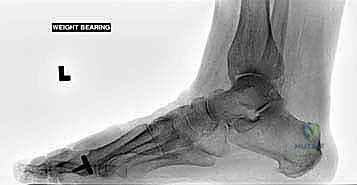

جراحة مفصل إبهام القدم الصناعي الجزئي (BioPro) لعلاج التهاب مفصل إصبع القدم الكبير: دليل شامل من الأستاذ الدكتور محمد هطيف

تعرف على جراحة مفصل إبهام القدم الصناعي الجزئي (Hemiarthroplasty) لعلاج التهاب المفصل الكبير (Hallux Rigidus) مع الأستاذ الدكتور محمد هطيف …